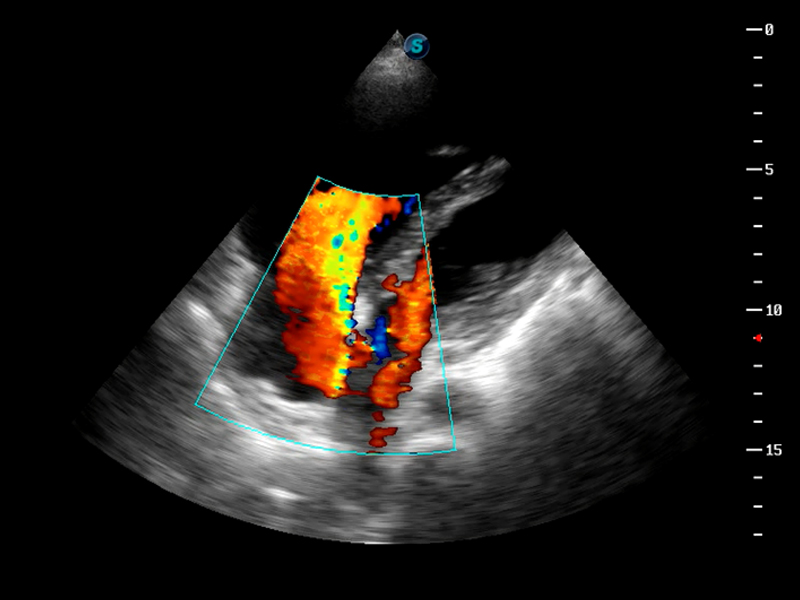

S9便携式彩色多普勒超声诊断仪是公海贵宾会员检测中心医疗研发的高端便携彩超设备,外观设计新颖、产品性能卓越。S9在便携超声领域采用了突破传统的触摸屏交互设计,并以先进的软件硬件技术和设计理念,为您带来清晰的图像质量、稳定的工作性能和便捷的操作体验。

AutoC智能血流追踪